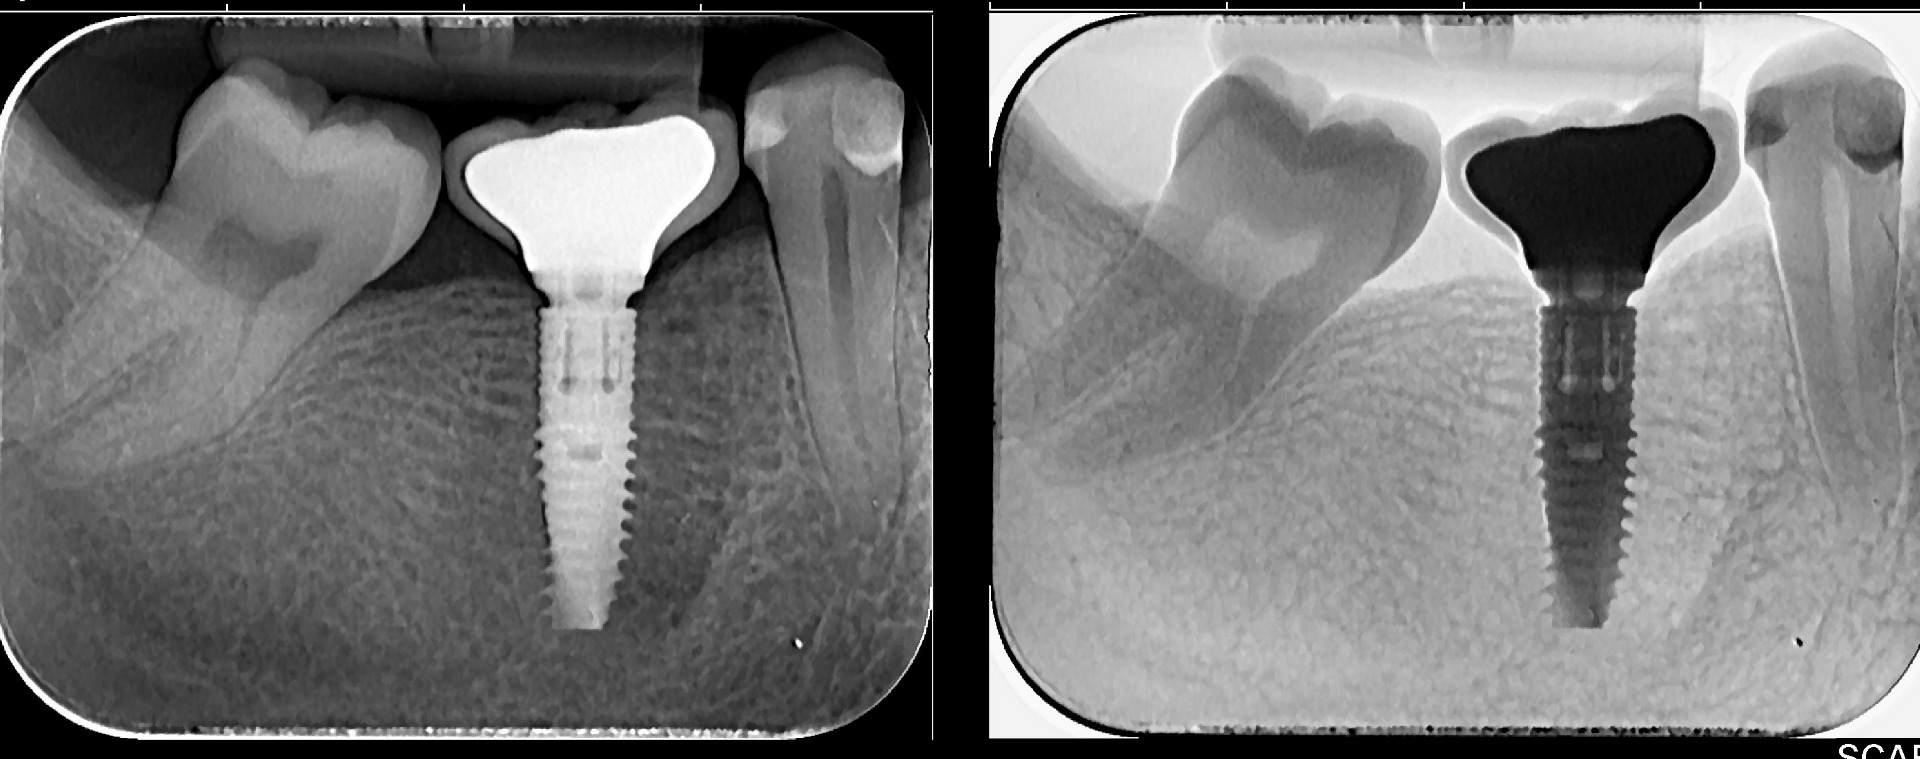

Implantul dentar este echivalentul unui șurub care se inseră în os, în locul dinților lipsă, având practic rolul unei rădăcini artificiale. În urma unui proces de osteosinteză, implantul dentar se integrează în os, astfel ca, după un interval de 3-6 luni, să se poată realiza lucrarea protetică finală.

Atunci când oferta osoasă nu este suficientă, este posibil ca înainte sau în timpul intervenției de inserare a implantului să fie nevoie de efectuarea unor proceduri suplimentare: adiții și reconstrucții osoase sau sinus lift.